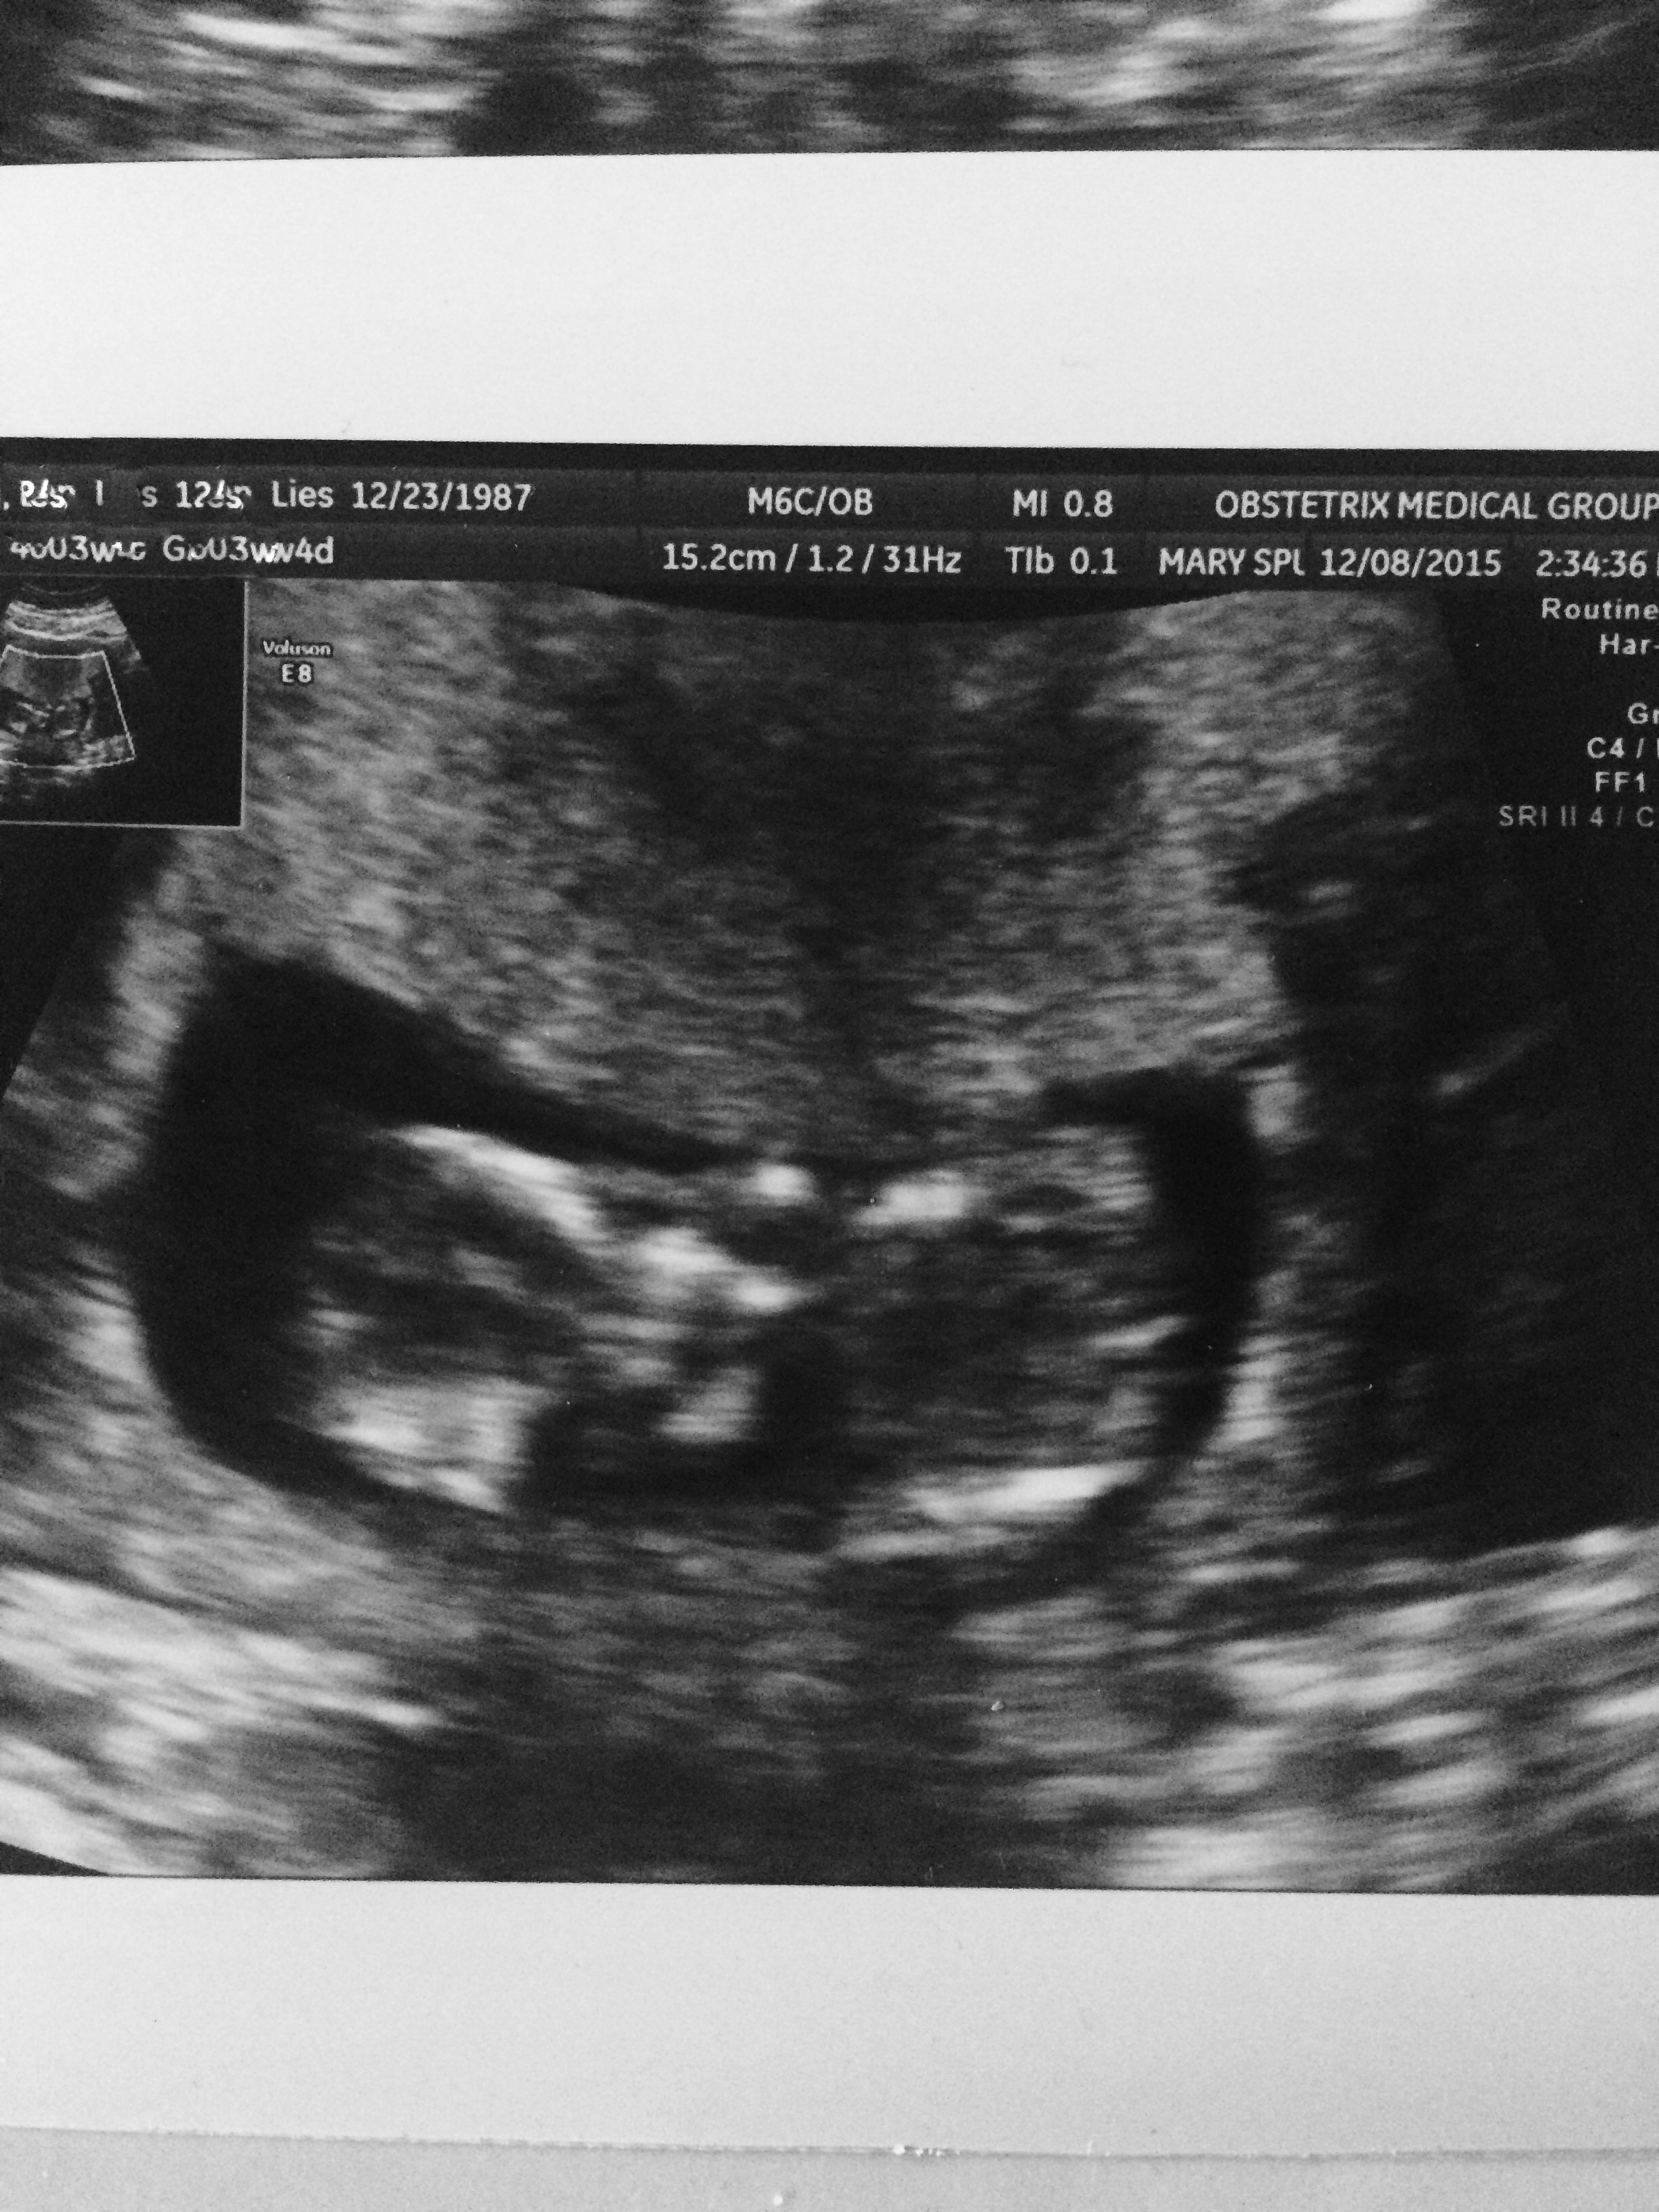

Had unscheduled ultrasound due to unexplained bleeding. Still don't know why I'm spotting (grr) but both babies were okay. 14+4 at the time of the scan. Baby A refused to face the camera.